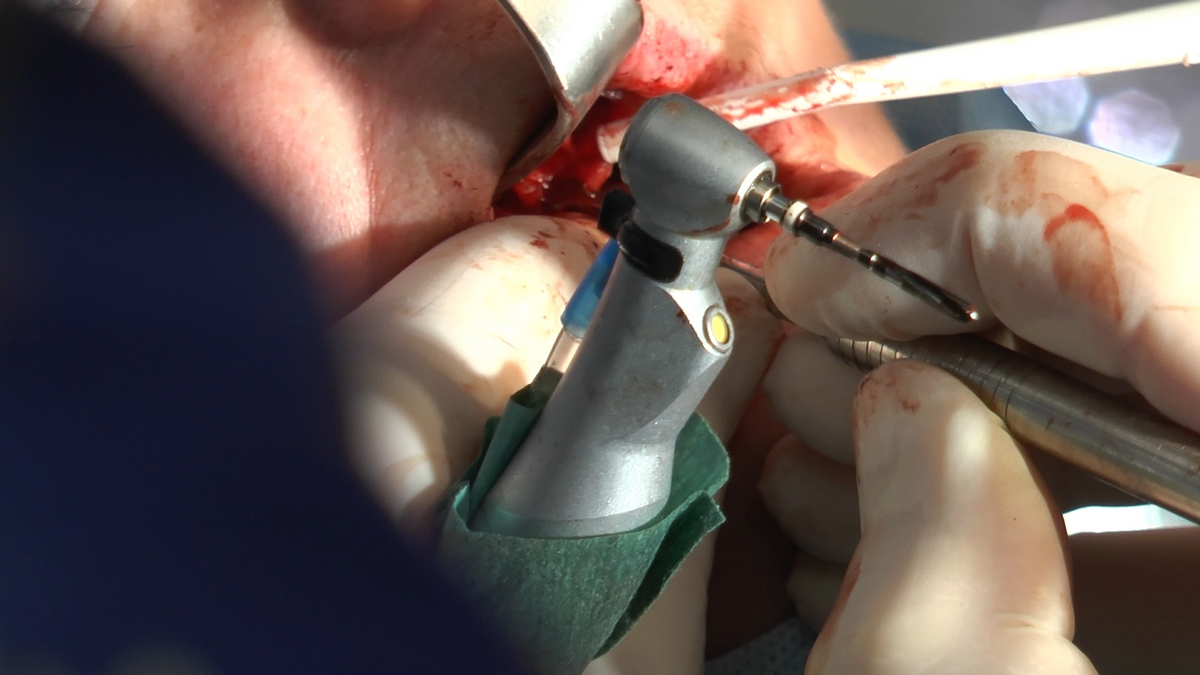

W trakcje dwóch dni zabiegowych, piątek i sobota, 5 i 6 października 2018 roku, lekarze uczestniczący w 6 Sesji VI Sezonu, wykonali wiele zabiegów o wysokim stopniu trudności. Przeprowadzili je pod kierunkiem Mentorów Instytutu Vivadental – dr n.med. Violetty Szycik, dr n.med. Magdaleny Kisłowskiej-Syryczyńskiej oraz dr Małgorzaty Piotrowskiej.

Wprowadziliśmy łącznie 25 implantów w tym wykonaliśmy:

zabiegi odsłonięcia 10 implantów wprowadzonych przez uczestników Practiculum,